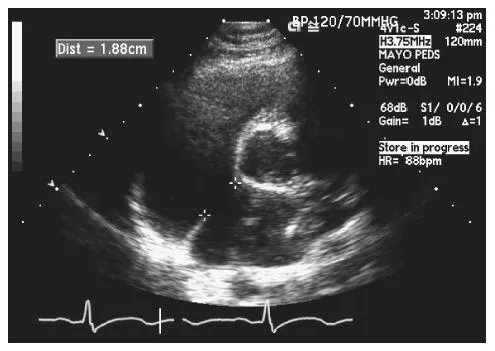

Transthoracic echocardiography is invaluable in the diagnosis of secundum ASD. Even if the defect itself cannot be visualized, the hemodynamic consequence of the shunt can be assessed by an evaluation of the right heart size and function. Identification of the defect by surface echocardiogram is influenced by the size of the defect. The subcostal window provides a good look at the atrial septum and should be used. The parasternal short axis view at the base of the heart may also demonstrate the defect (Fig. 1.3). The apical four-chamber view can be misleading; when the atrial septum is parallel to the echocardiographic signal, drop out may occur. Tilting the apical view off-axis will align the atrial septum at an angle and allow for better 2-D and color interrogation. The degree of tricuspid valve regurgitation should be assessed, as this may influence the mode of repair. The pulmonary artery pressures should be estimated via the modified Bernoulli equation (ΔP = 4v2), with the systolic pressure calculated from the tricuspid valve regurgitation velocity (assuming there is no pulmonary stenosis) and the diastolic pressure estimated from the pulmonary regurgitation end-diastolic velocity. There is very little usefulness in calculating the ratio of pulmonary blood flow to systemic blood flow (Qp:Qs) by echocardiography, as the measurements are often inaccurate.

Fig. 1.3 Transthoracic echocardiogram, parasternal short axis view. The atrial septal defect measures 1.88 cm.